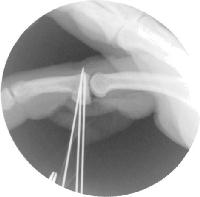

Here, the graft has been harvested and sculpted to fit the remaining joint. Three 0.035" K wires are in place for provisional fixation.

Intraoperative fluoroscopy confirms proper realignment of the joint with the bone graft in place.